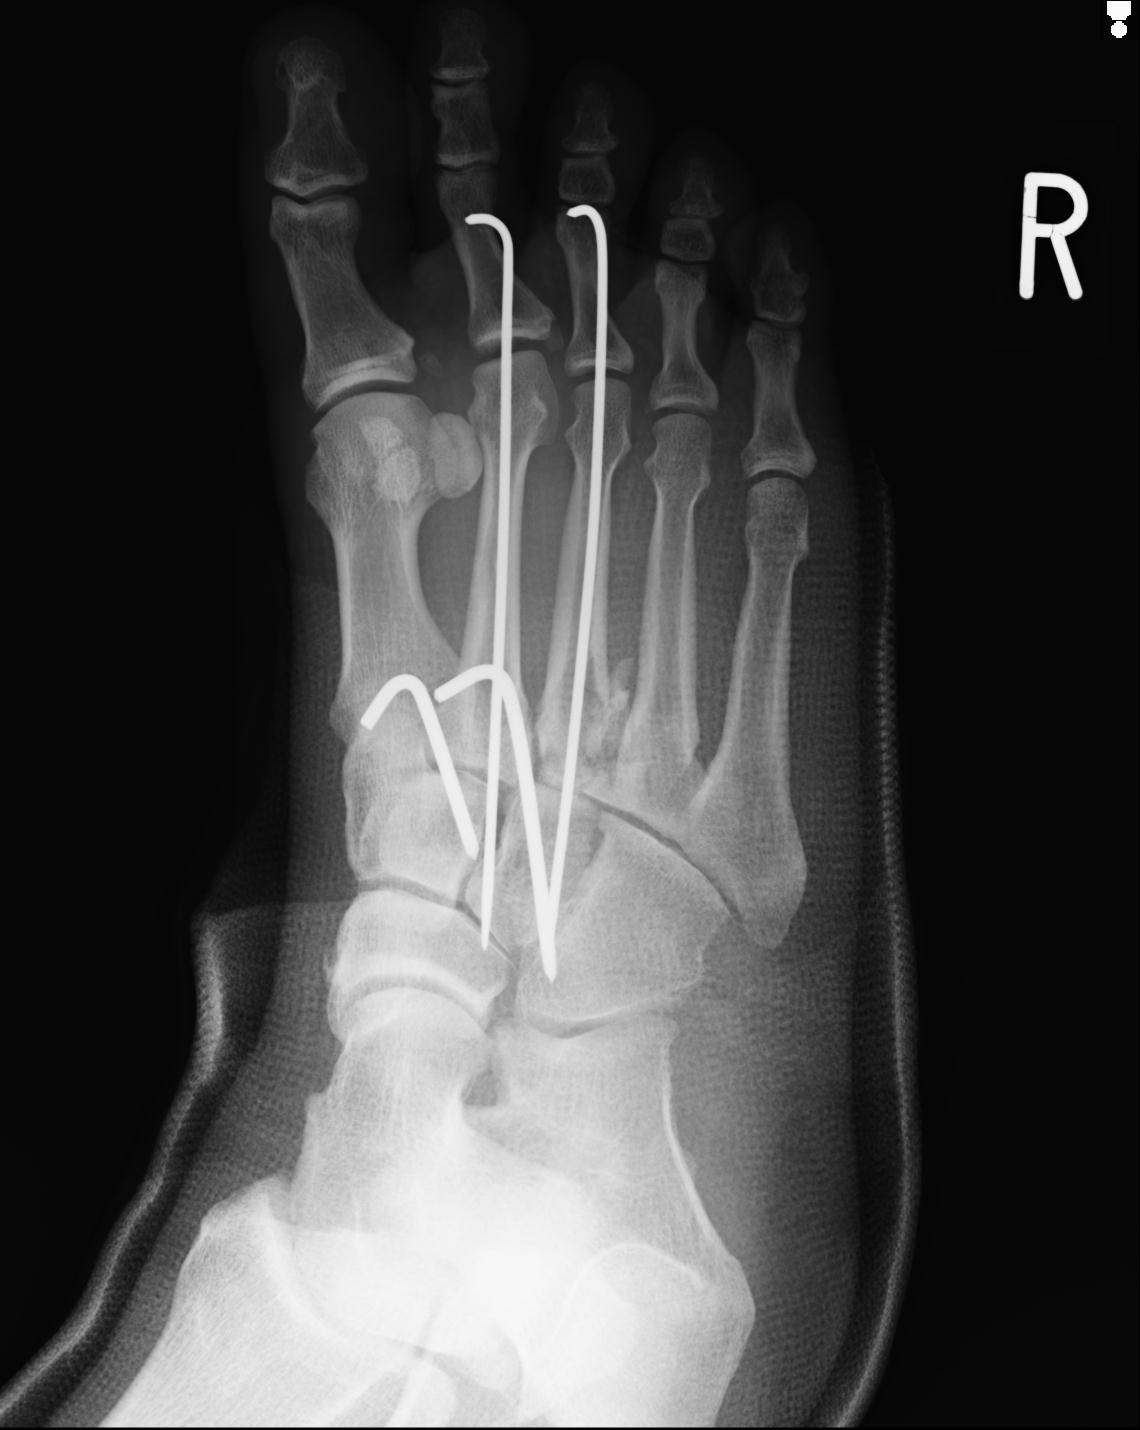

103177 3/11 右足 2R 3/16 右足 2R リスフラン脱臼 55歳男性